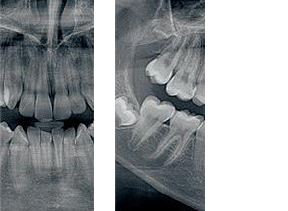

Skany cienkowarstwowe (funkcja 2D+) oferują większą możliwość

niż standardowy obraz dwuwymiarowy.

Dzięki wysokiej ostrości skanom wycinkowym lekarz szybciej

i precyzyjniej może ustalić położenie zębów nadliczbowych

i zatrzymanych, oceni zmiany wierzchołkowe, a także określi relację korzenia z wyrostkiem zębowym.